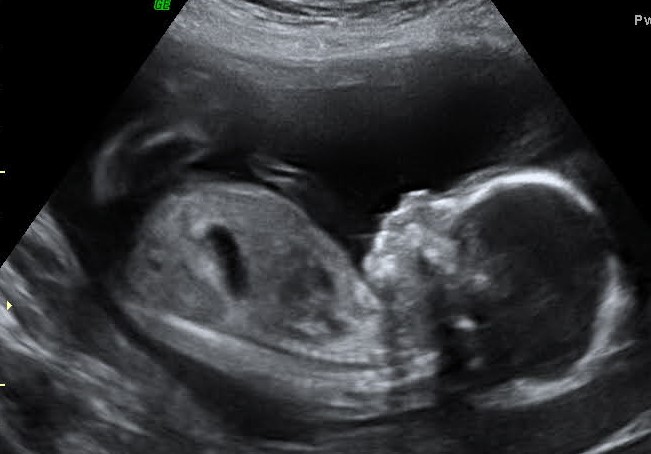

It's a boy!

Plain as day there it is. Were so excited and hoping to have a name picked out soon. Were working on finishing our registry and to have the links for that soon.